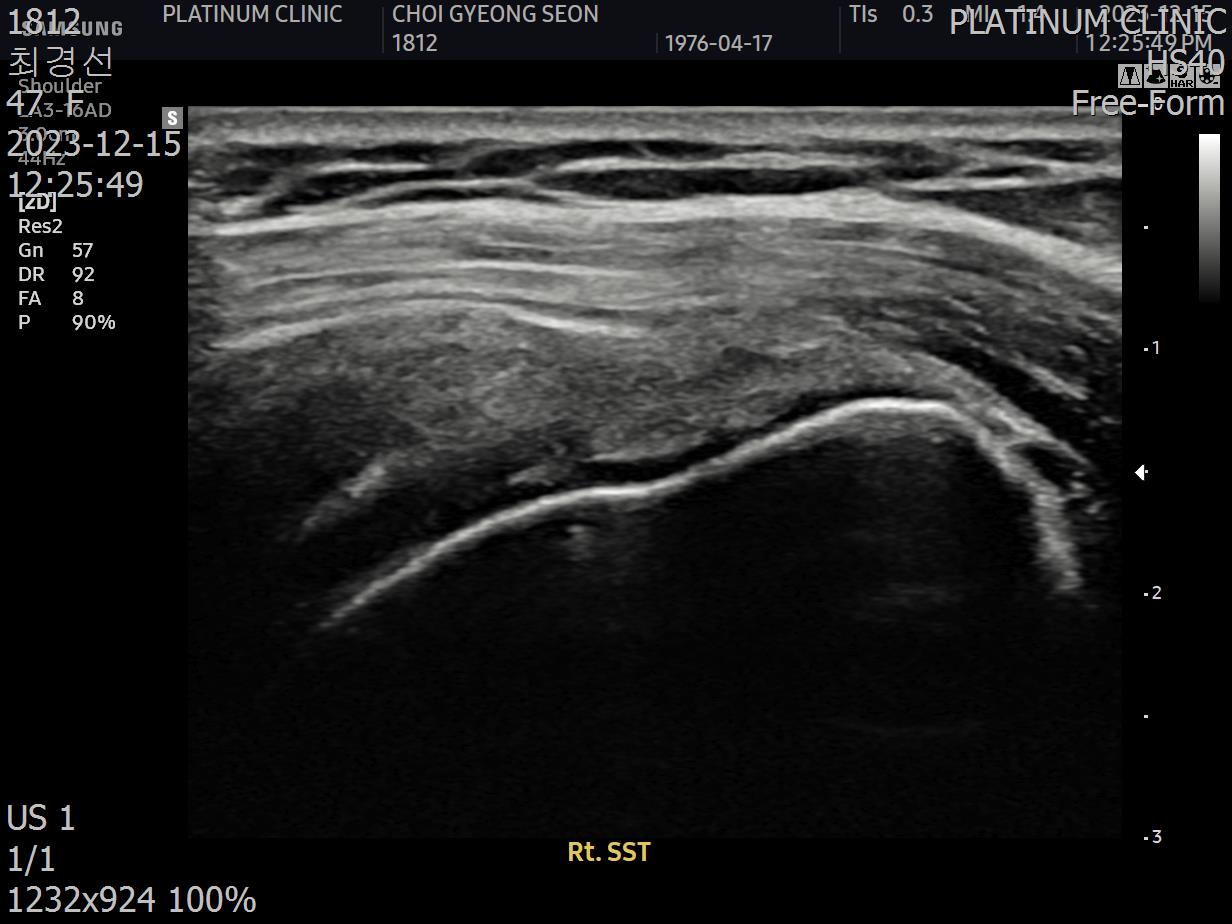

초음파 검사로 확인할 수 있습니다.

치료 전 초음파에서 검게 보이던 파열 부위가, 치료 후에는 정상 인대처럼 하얗게 보입니다. 이것이 구조적 회복의 증거입니다.

안 아파요"라는 주관적 느낌만으로 치료 완료를 판단하면 안 됩니다. 영상으로 확인된 구조적 회복이 있어야 진정한 치료입니다.

12주차: 초음파로 확인된 '재생'

마지막 주사로부터 6주 후, 팔로우업 검사를 진행했습니다.

초음파 결과:

이전에 검게 보이던 파열 부위가 하얗게 재생됨

인대 두께가 정상 범위로 회복됨

주변 염증 소견 소실

세 가지 기준이 모두 충족되었습니다.

환자분, 이번에는 진짜 치료가 끝났습니다. 초음파에서도 재생이 확인되었고요. 이제 재활 운동만 꾸준히 하시면 됩니다.